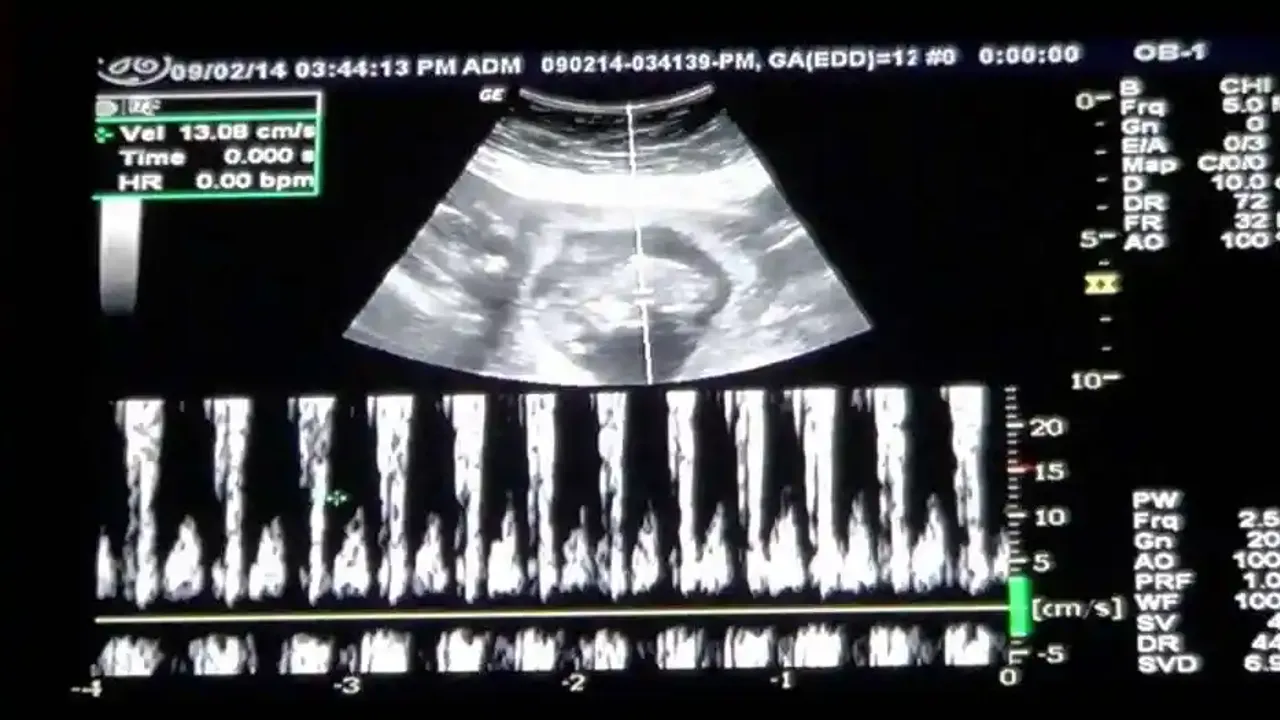

Bebeğin kalp atışları, dakikada 100 ila 160 arasındadır. Bebeğin kalp atışları, gebeliğin ilerleyen dönemlerinde yavaş yavaş azalır ve doğuma yakın dakikada 120 ila 160 arasındadır.